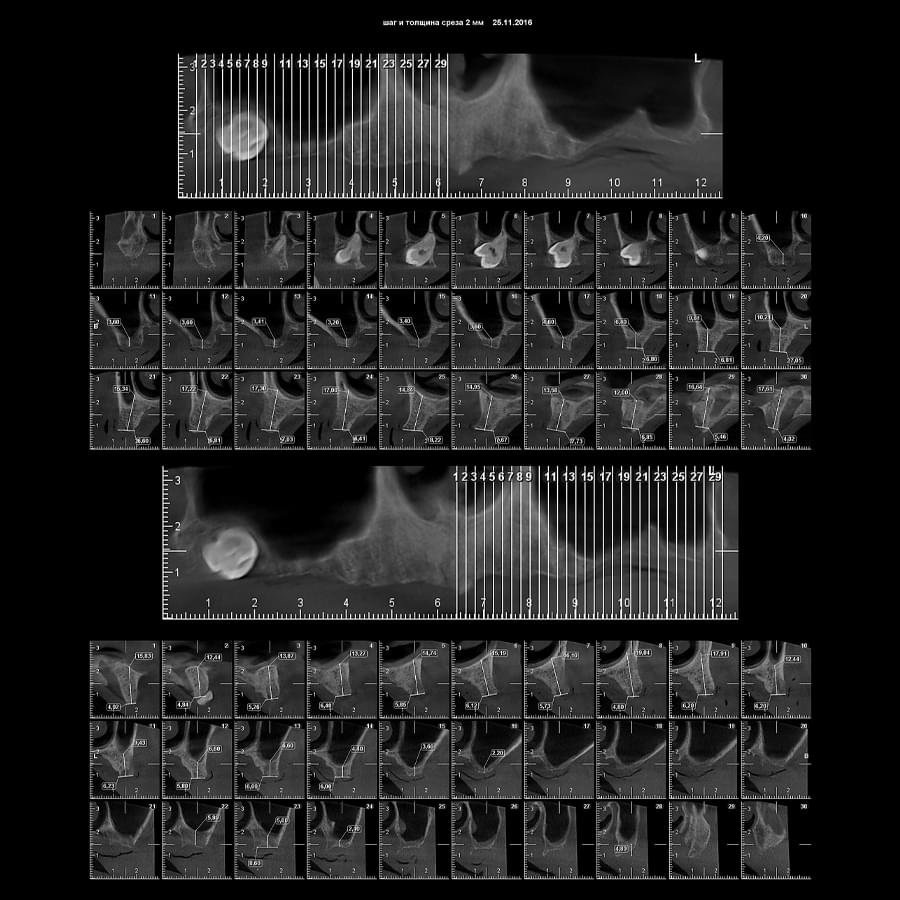

3D цефалометричний аналіз є сучасною технологією, яка дозволяє отримувати точніші,

комплексніші та надійніші дані про зубну та скелетну структуру. Ця технологія може стати

великим кроком в перед для ортодонтів, які хочуть забезпечити найкраще можливе лікування

своїх пацієнтів.

Основні переваги 3D цефалометричного аналізу:

Точність: 3D цефалометричний аналіз забезпечує точніше визначення розмірів та відстаней між

зубами та кістковими структурами.

Комплексність: ця технологія дозволяє отримувати детальні дані про різні структури, такі як

кістка та м'язи, що дозволяє ортодонтам докладніше досліджувати деякі патології та планувати

лікування.

Надійність: 3D цефалометричний аналіз дозволяє отримувати надійніші результати, оскільки

виключає можливість помилок, пов'язаних зі спотворенням або перекриттям зображень.